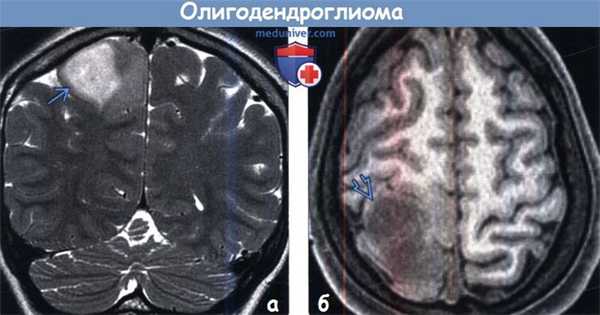

(а) МРТ, Т2-ВИ, корональный срез: в структуре белого вещества с вовлечением коры определяется внешне отграниченное от окружающих структур гиперинтенсивное объемное образование. При резекции опухоли была диагностирована олигодендроглиома II степени злокачественности по классификации ВОЗ (grade II), а также делеция 1p, 19q. Делеции 1p, 19q и мутация IDH 1 связаны с более высокой выживаемостью.

(б) MPT, Т1-ВИ, аксиальный срез: у того же пациента определяется гипоинтенсив-ное объемное образование, распространяющееся на кору и глубокое белое вещество правой лобно-теменной области. После введения контраста его накопления образованием выявлено не было. Около 50% олигодендроглиом grade II характеризуются контрастированием.

(а) МРТ, Т2-ВИ, аксиальный срез: определяется неоднородно гиперинтенсивное объемное образование, распространяющееся на кору и субкортикальное белое вещество, оказывающее умеренный масс-эффект на окружающие структуры. Данная картина очень похожа на олигодендроглиому. При резекции опухоли была диагностирована анапластическая олигодендроглиома. Grade II олигодендроглиом не может быть достоверно отдифференцирована от grade III при рутинной диагностической визуализации. Могут быть полезны МР-спектроскопия и МР-перфузия.

(б) МРТ, постконтрастное Т1 -ВИ, корональный срез: определяется гетерогенное контрастирование олигодендроглиомы grade II, расположенной в лобной доле.